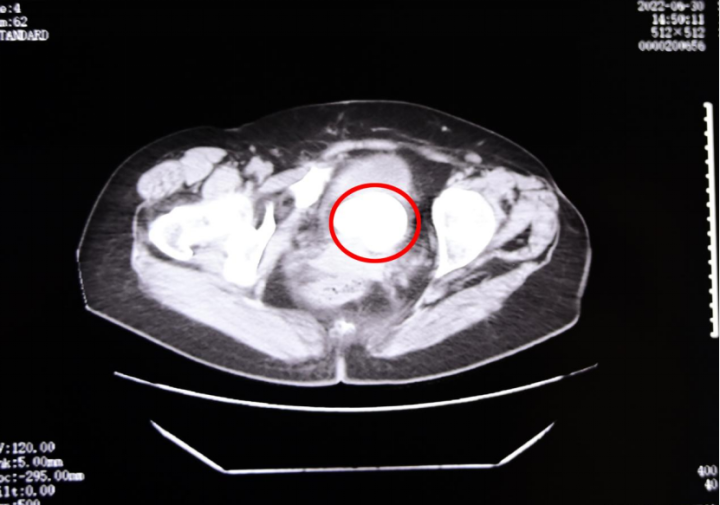

患者术前影像图,红圈部分为结石

就在一个月前,今年50岁的季女士突然出现尿频、尿急、尿痛症状,偶有血尿,本以为患上了尿路感染,遂前往重庆医药高专附一院(重庆市第六人民医院)泌尿外科就诊,可检查结果却吓了季女士一大跳——自己膀胱里竟长有一个直径6厘米的结石!

尿结石比鸡蛋还大,在临床已属于巨大结石的范畴,必须尽快安排手术。市六院泌尿外科主任靳文生一面为患者开具了口服药物,缓解季女士相关症状,一面与患者及家属充分沟通,为其制定了“经尿道膀胱超声弹道碎石术”手术方案,希望彻底解除季女士身体里的这颗“定时炸弹”。